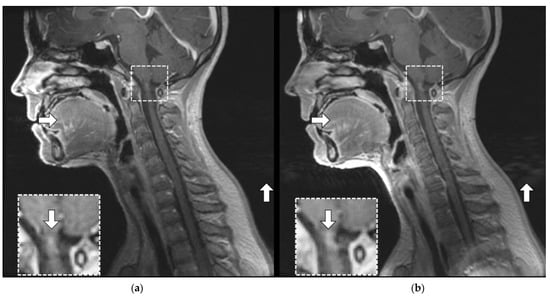

3.3.2. Artifact Enhancement

3.3.3. Coil Placement